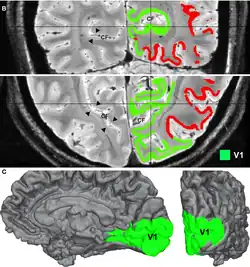

Adaptation is caused by the prolonged viewing of unchanging patterns. IOT in adaptation within the primary visual cortex has been explored. IOT as the ability to experience aftereffects in the eye that did not view the adapting pattern occurring in the primary visual cortex (V1) of cats. IOT may be mediated by callosal connections between the two hemispheres, and is not dependent on the conventional binocularity of neurons. The study attempted to provide the physiological evidence to the existence of IOT.[14] There is also FMRI evidence that observed binocular visual interactions in the visual cortex in humans.[15]